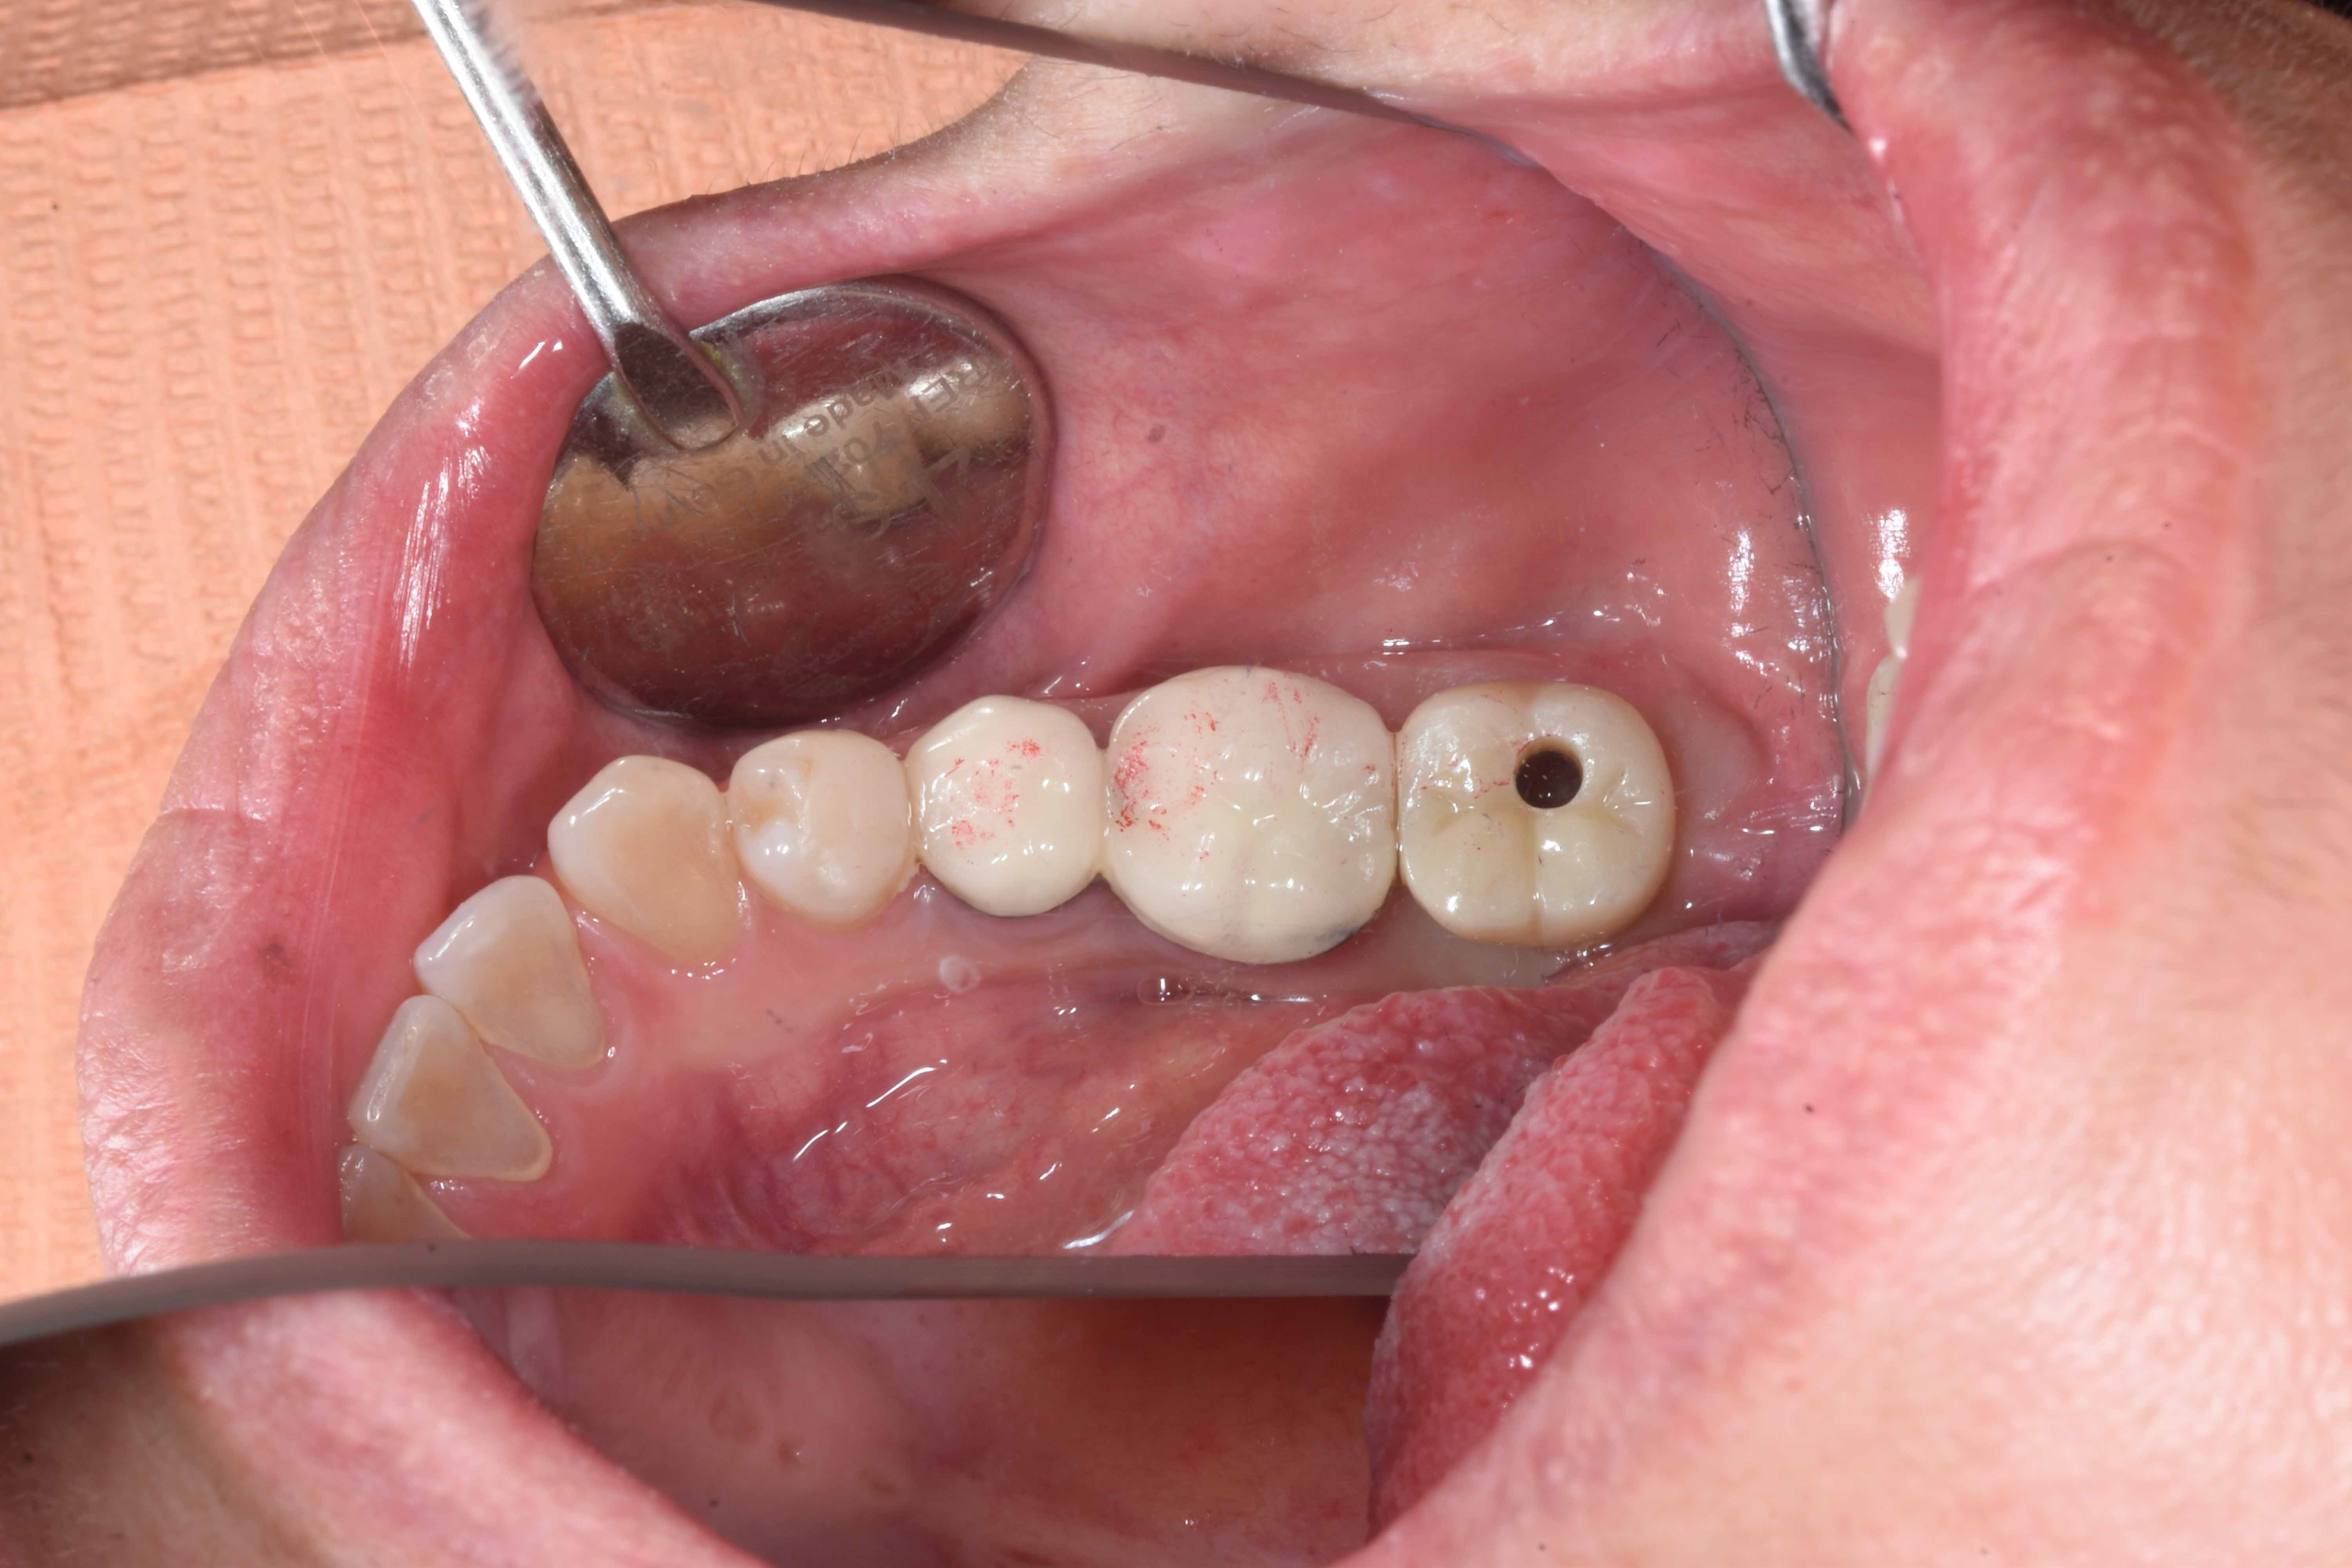

案例五

立即拔除牙根不好的牙齒

醫生透過電腦斷層評估骨頭狀況決定植入的植體所放的寬度與深度

2-3月癒合,取下癒合螺帽,透過數位口掃至技公所製作假牙

2-3個月癒合,7-10天完成假牙 ,試戴、調整咬合高度並鎖上,封填,完成